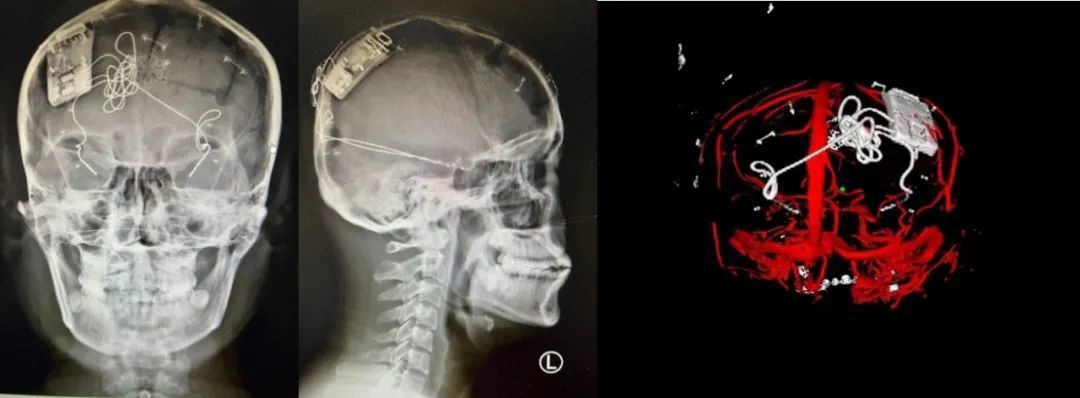

本次手術(shù)過程順利,術(shù)中刺激器各項(xiàng)指標(biāo)均工作正常,術(shù)后重建顯示電極位置精準(zhǔn),腦電信號清晰?;颊邽槟行?,入院后診斷為雙側(cè)顳葉癲癇,此類癲癇為開顱手術(shù)的相對禁忌癥,在藥物無法控制的情況下,傳統(tǒng)治療效果欠佳 。

術(shù)前經(jīng)過宣武醫(yī)院癲癇多學(xué)科專家團(tuán)隊(duì)詳細(xì)的臨床評估,包括視頻腦電監(jiān)測、頭顱磁共振及三維 CT 掃描、腦核醫(yī)學(xué)檢查等,全面評估了患者病情及致癇灶定位情況。

由于患者臨床診斷為雙側(cè)顳葉癲癇伴海馬硬化,無法通過致癇灶切除等傳統(tǒng)外科手術(shù)方式獲益,決定進(jìn)行閉環(huán)反應(yīng)性神經(jīng)刺激系統(tǒng)植入手術(shù)治療。并根據(jù)閉環(huán)神經(jīng)刺激技術(shù)特點(diǎn),為患者“量身定制”植入方案,尤其是電極植入位點(diǎn)和脈沖發(fā)生器固定部位等,為手術(shù)的順利實(shí)施奠定了良好基礎(chǔ)。

團(tuán)隊(duì)根據(jù)術(shù)前計(jì)劃,在手術(shù)機(jī)器人輔助下完成雙海馬長軸電極及 IPG 植入,術(shù)后重建顯示電極位置精準(zhǔn),腦電信號清晰。術(shù)后第二天,患者即下床活動,身體狀況恢復(fù)良好。